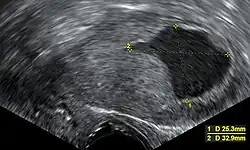

Nos Estados Unidos, tem sido cada vez mais usada a ecografia transvaginal para examinar a espessura do endométrio em mulheres com hemorragias pós-menopausa, de modo a auxiliar o diagnóstico de cancro do endométrio.[38] No Reino Unido, tanto a biópsia endometrial quanto a ecografia transvaginal, usadas em conjunto, são o tratamento padrão para o diagnóstico de cancro do endométrio.[15] A homogeneidade do tecido visível na ecografia transvaginal pode ajudar a indicar se a espessura é cancerosa. As descobertas da ecografia por si só não são conclusivas em casos de cancro do endométrio, pelo que deve ser usada em conjunto com outro método de rastreio (por exemplo, biópsia endometrial). Outros exames imagiológicos são de uso limitado. As TAC são usadas para imagens pré-operatórias de tumores que parecem avançados no exame físico ou têm um subtipo de alto risco (com alto risco de metástase).[39] Eles também podem ser usados para investigar doenças extrapélvicas.[15] Uma ressonância magnética pode ser útil para determinar se o cancro alastrou-se para o colo do útero ou se é um adenocarcinoma endocervical.[39] A ressonância magnética também é útil para examinar os nódulos linfáticos próximos.[15]